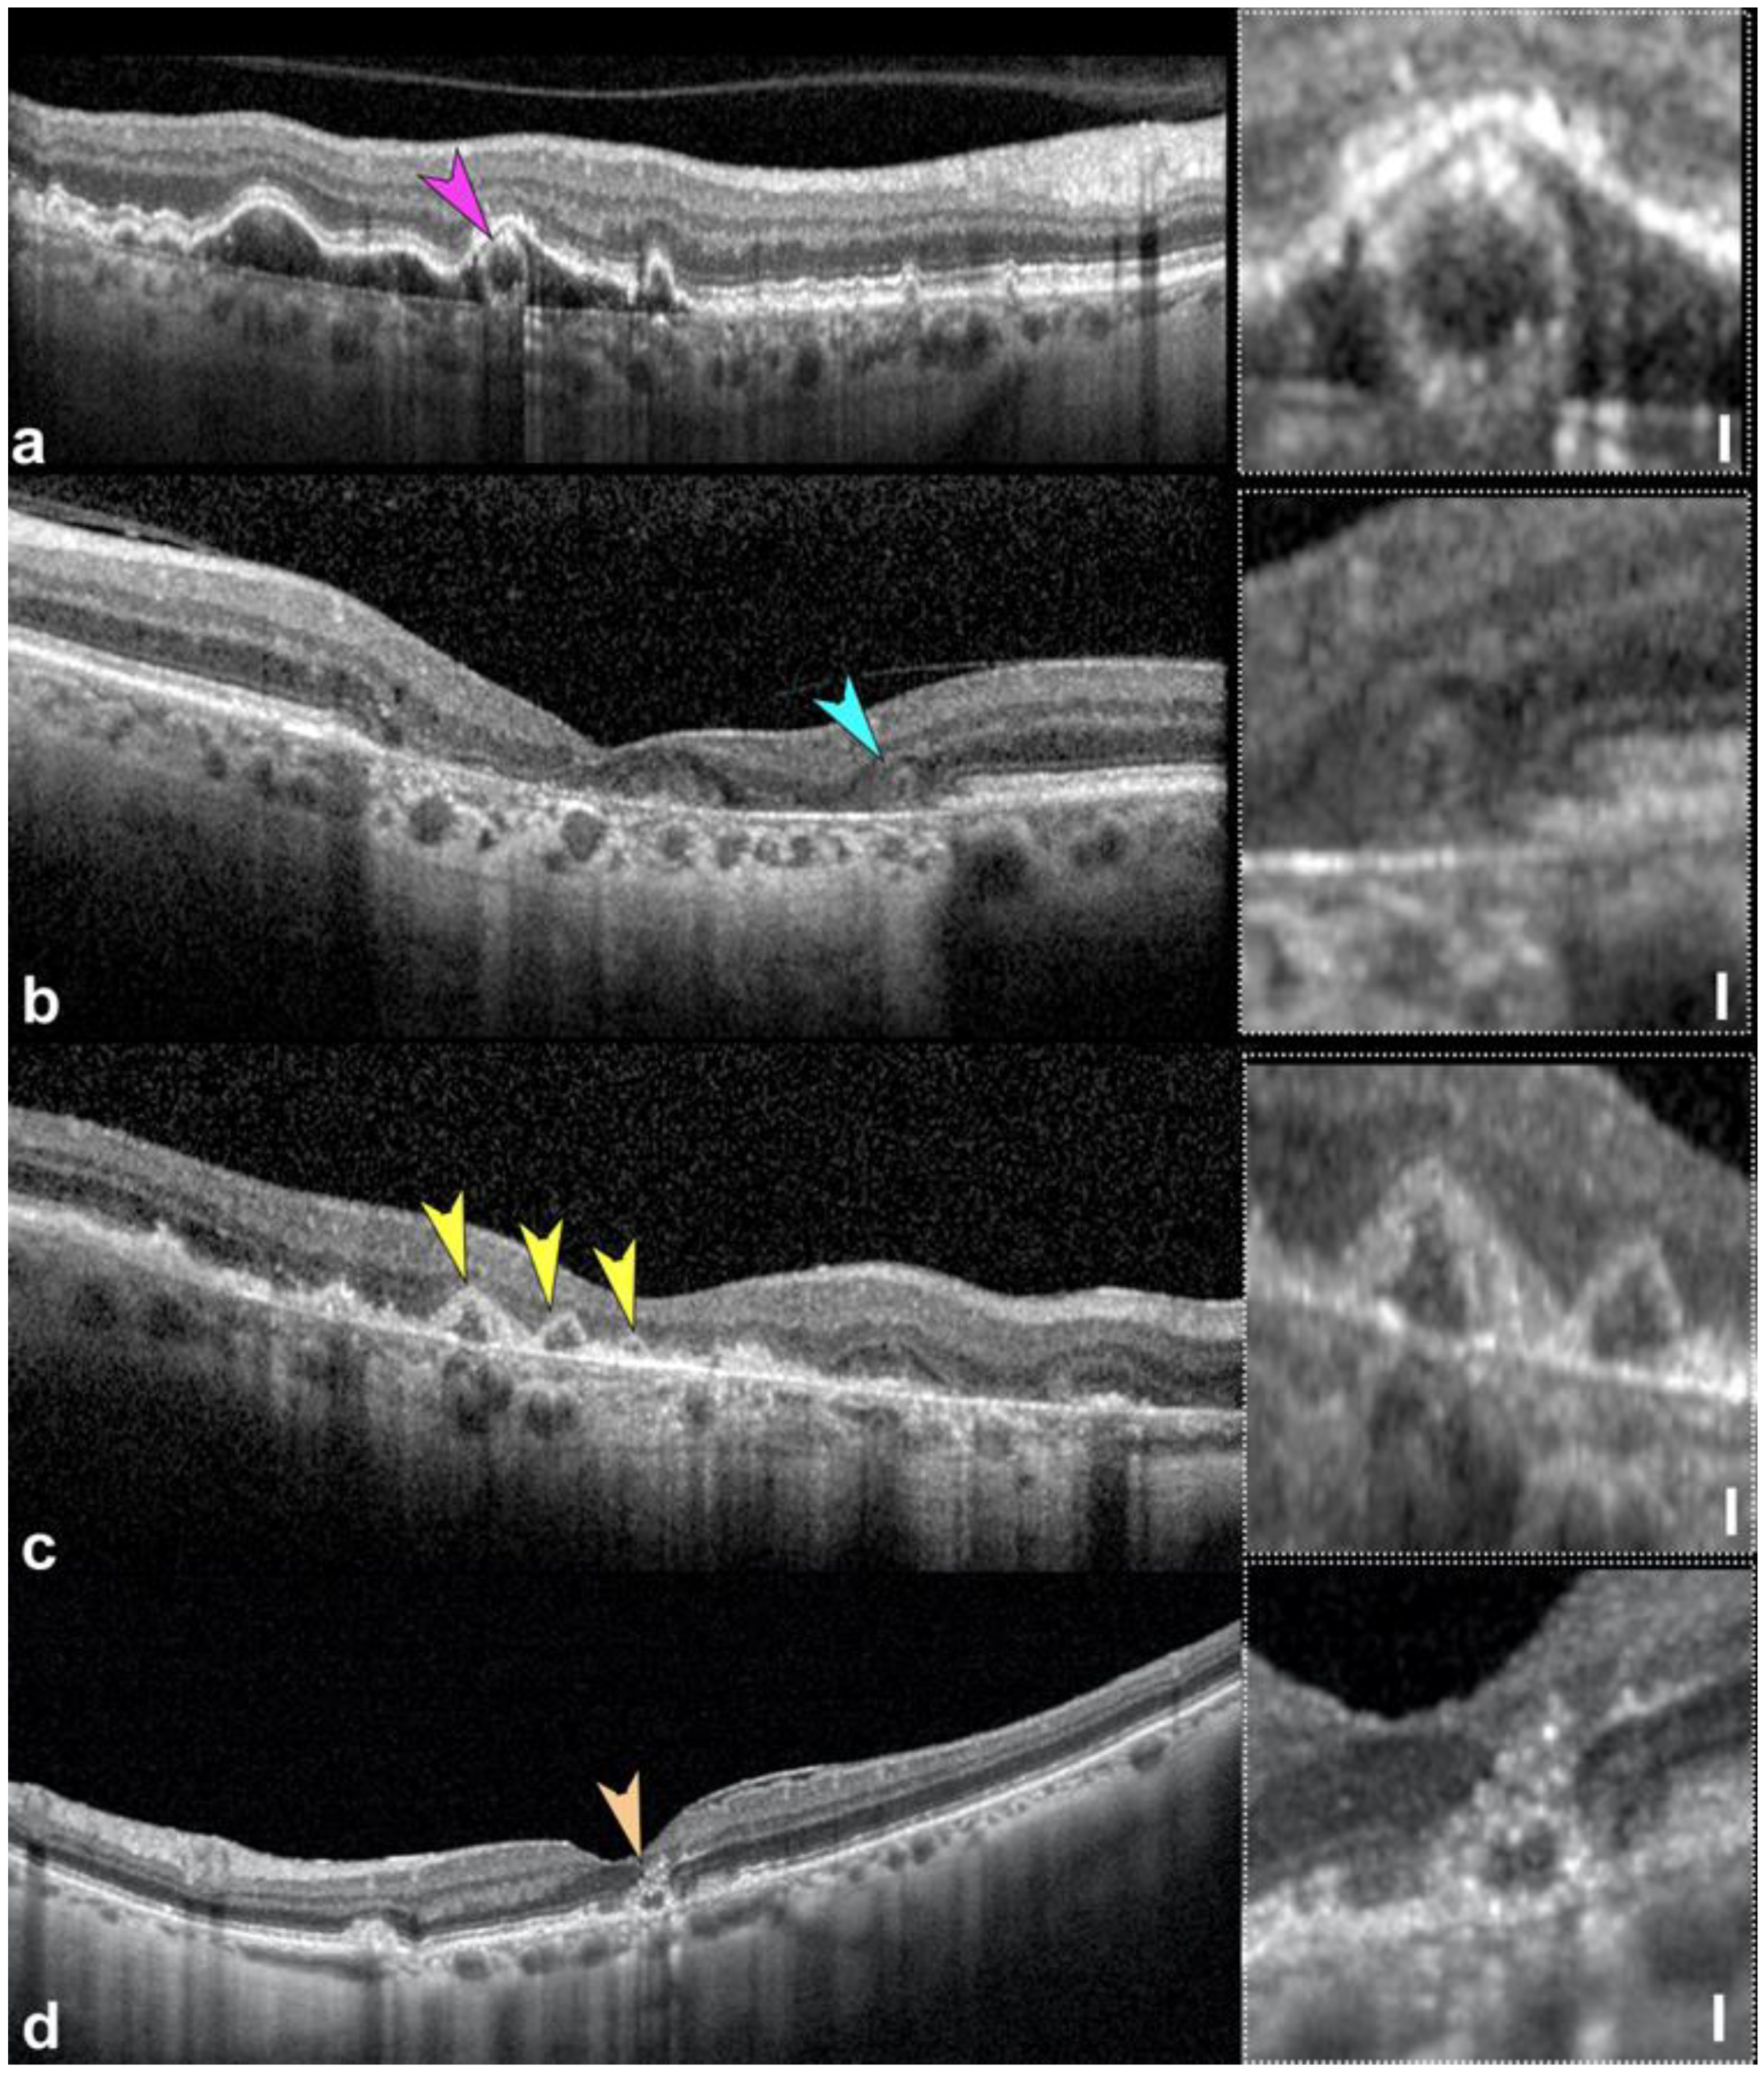

- Pang, C.E.; Messinger, J.D.; Zanzottera, E.C.; Freund, K.B.; Curcio, C.A. The onion sign in neovascular age-related macular degeneration represents cholesterol crystals. Ophthalmology 2015, 122, 2316–2326. [Google Scholar] [CrossRef]

- Fragiotta, S.; Fernandez-Avellaneda, P.; Breazzano, M.P.; Curcio, C.A.; Leong, B.C.S.; Kato, K.; Yannuzzi, L.A.; Freund, K.B. The Fate and Prognostic Implications of Hyperreflective Crystalline Deposits in Nonneovascular Age-Related Macular Degeneration. Investig. Ophthalmol. Vis. Sci. 2019, 60, 3100–3109. [Google Scholar] [CrossRef]

- Querques, G.; Georges, A.; Ben Moussa, N.; Sterkers, M.; Souied, E.H. Appearance of regressing drusen on optical coherence tomography in age-related macular degeneration. Ophthalmology 2014, 121, 173–179. [Google Scholar] [CrossRef]

- Fragiotta, S.; Fernandez-Avellaneda, P.; Breazzano, M.P.; Yannuzzi, L.A.; Curcio, C.A.; Freund, K.B. Linear and planar reflection artifacts on swept-source and spectral-domain optical coherence tomography due to hyperreflective crystalline deposits. Graefes Arch. Clin. Exp. Ophthalmol. 2020, 258, 491–501. [Google Scholar] [CrossRef]

- Liu, J.; Laiginhas, R.; Shen, M.; Shi, Y.; Li, J.; Trivizki, O.; Waheed, N.K.; Gregori, G.; Rosenfeld, P.J. Multimodal Imaging and En Face OCT Detection of Calcified Drusen in Eyes with Age-Related Macular Degeneration. Ophthalmol. Sci. 2022, 2, 100162. [Google Scholar] [CrossRef] [PubMed]

- Suzuki, M.; Curcio, C.A.; Mullins, R.F.; Spaide, R.F. Refractile drusen: Clinical imaging and candidate histology. Retina 2015, 35, 859–865. [Google Scholar] [CrossRef] [PubMed]

- Oishi, A.; Thiele, S.; Nadal, J.; Oishi, M.; Fleckenstein, M.; Schmid, M.; Holz, F.G.; Schmitz-Valckenberg, S. Prevalence, natural course, and prognostic role of refractile drusen in age-related macular degeneration. Investig. Ophthalmol. Vis. Sci. 2017, 58, 2198–2206. [Google Scholar] [CrossRef]

- Tan, A.C.S.; Pilgrim, M.G.; Fearn, S.; Bertazzo, S.; Tsolaki, E.; Morrell, A.P.; Li, M.; Messinger, J.D.; Dolz-Marco, R.; Lei, J.; et al. Calcified nodules in retinal drusen are associated with disease progression in age-related macular degeneration. Sci. Transl. Med. 2018, 10, eaat4544. [Google Scholar] [CrossRef]